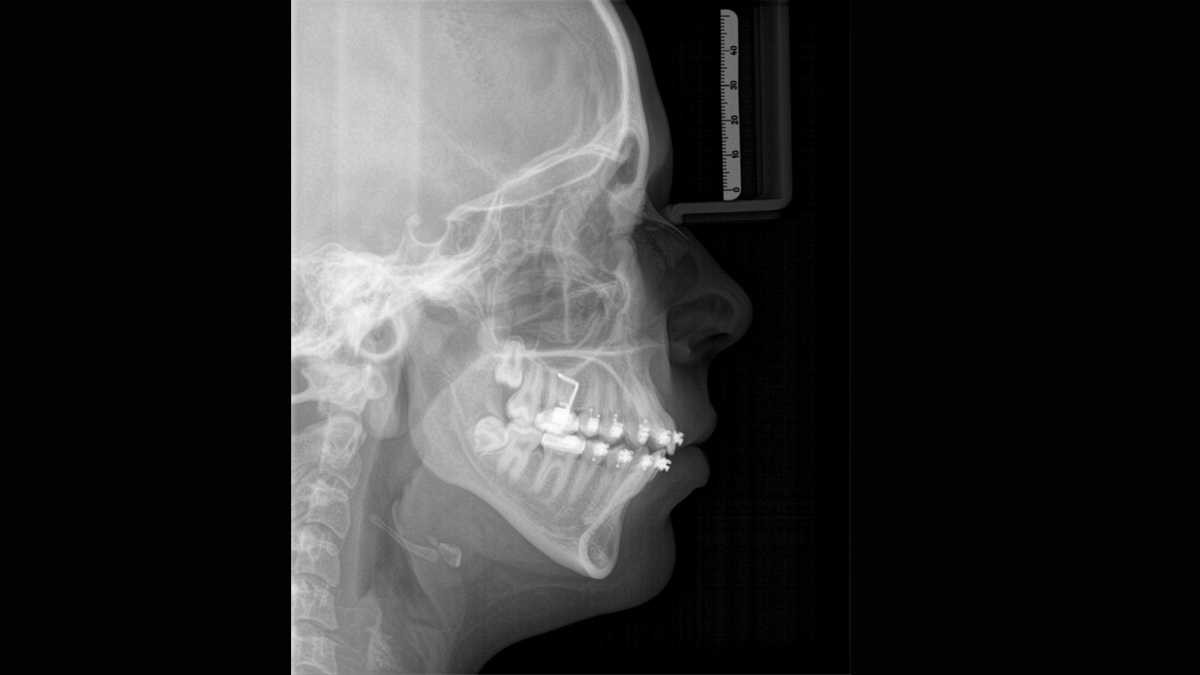

Imagen cefalométrica

Orthophos SL 3D ofrece la posibilidad de instalar un brazo cefalométrico en cualquier momento. Para asegurarse de que se ajusta a su sala de rayos X, el brazo puede montarse en el lado derecho o el lado izquierdo de la unidad.

Programas cefalométricos que cubren todas las necesidades ortodóncicas

Usando un sensor específico, obtiene imágenes laterales y simétricas, así como imágenes del carpo. En casos de dientes desplazados, podría recurrrir a los beneficios de las radiografías en 3D para determinar la localización exacta.